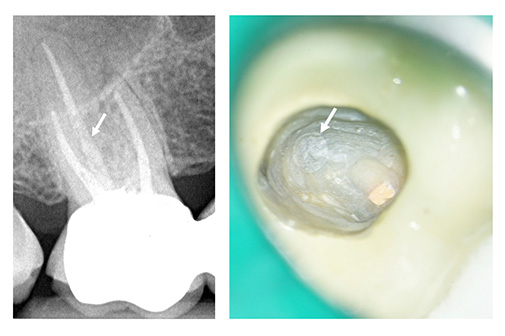

Adhäsiv befestigte Glasfaserstifte lassen sich in der Regel mit Hilfe von Langschaftrosenbohrern und unter direkter Sicht durch das Operationsmikroskop kontrolliert entfernen. Allerdings können sie präoperativ radiologisch nicht immer eindeutig identifiziert werden, da ihr Röntgenkontrast häufig nur schwer vom umgebenden Wurzelkanalfüllmaterial zu unterscheiden ist (Abb. 3a und b).

Abb. 3: a) Präoperative Einzelzahnaufnahme des Zahnes 16. Der palatinal inserierte Glasfaserstift ist radiologisch kaum erkennbar (Pfeil). b) Intraoperativ sichtbarer Glasfaserstift im palatinalen Wurzelkanal (Pfeil). Fotos: Franziska Haupt